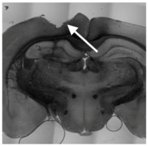

| Stage | Before Implantation | During Implantation | Post-Implant (<1 Week) | Post-Implant (>1 Week) |

| In vivo procedure | Acute | ![]() | Chronic | |

| Schematic view | ![]() | ![]() | ![]() | ![]() |

| Potential causes of damage |

| Induced effects |

![]() | ![]() | ![]() | ![]() | |

| Results |

| Proposed solutions |